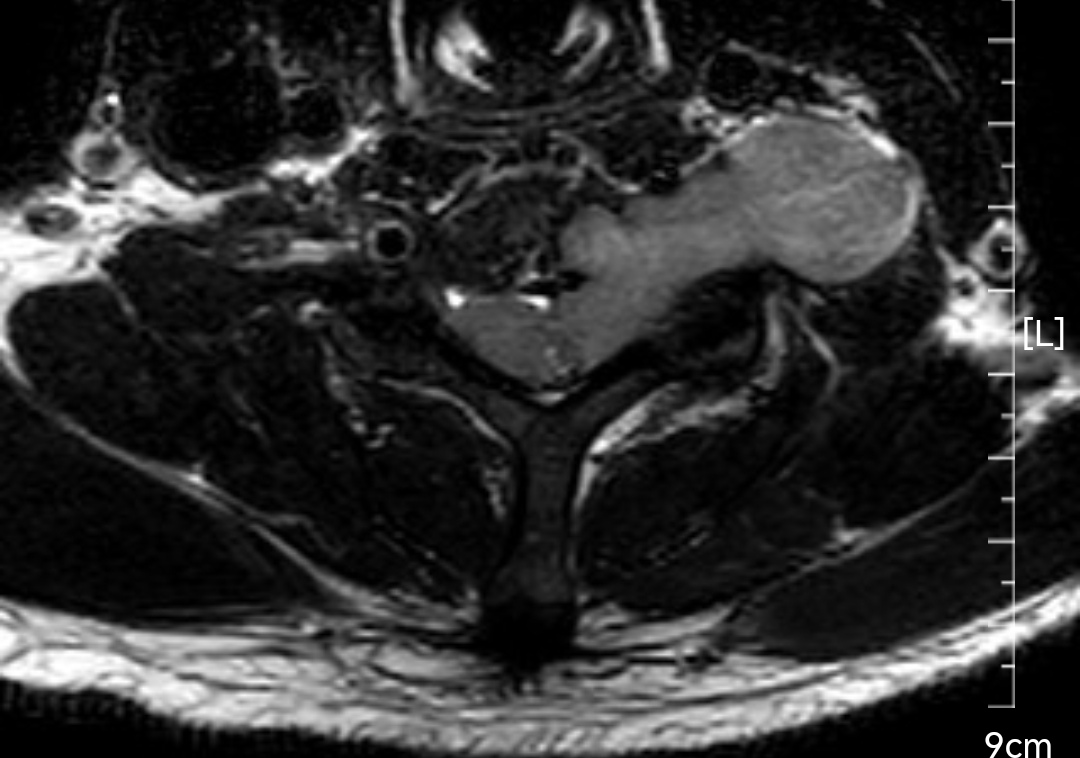

颈椎哑铃型神经纤维瘤,椎间孔汇合,安全又便于操作~